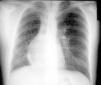

Radiología Caso en imagen:2

Caso en imagen:2

Case 2

FJ de Castro Garcíaa, JA. Santos Sánchezb, JA. Gutiérrez Díezb

a Centro Diagnóstico Recoletas Salamanca. Salamanca.

b Servicio de Radiodiagnóstico. Hospital Universitario de Salamanca. Salamanca. España.